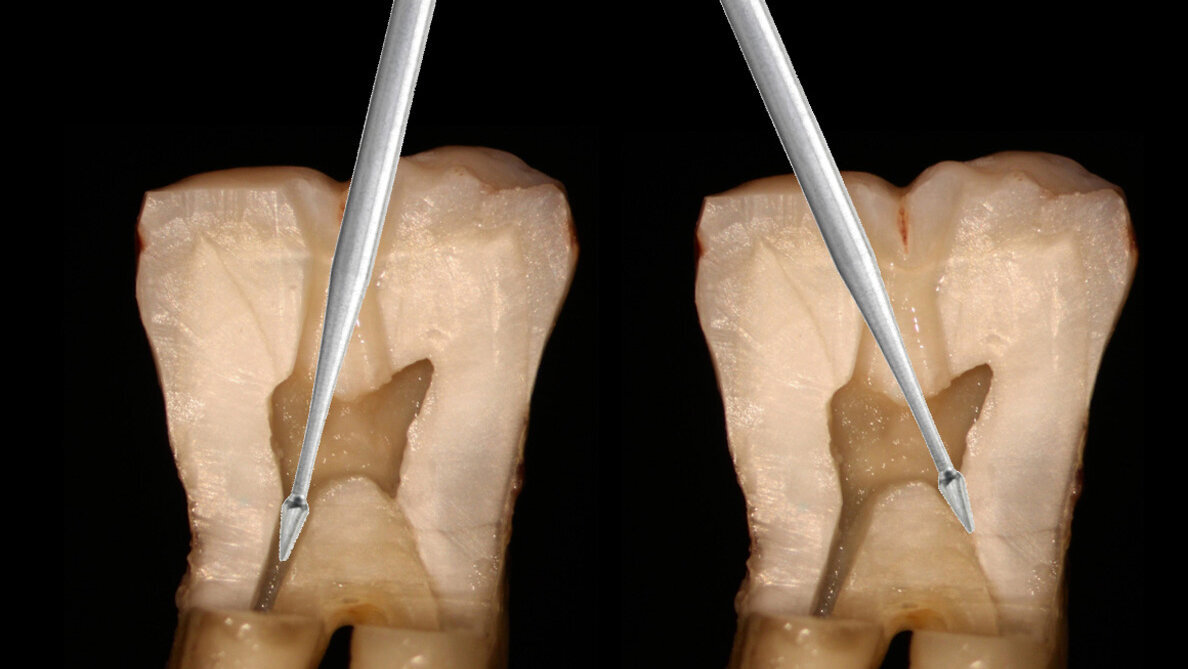

Fig. 3: An orifice-directed access conserves more tooth structure as it follows the direction of the canal, resulting in a smaller access opening and preservation of critical tooth.

Fig. 4: Orifice-directed access in a molar utilizing Endoguide burs to conserve tooth structure while giving straight line access into the canals.

The goal of endodontic access is to locate the canal orifices and allow straight-line access into those canals to permit instrumentation. Traditionally, endodontic access in molars recommended a large access that allowed the files to drop into the canal from a vertical direction essentially parallel to the long axis of that molar. Unfortunately, this approach removes a considerable amount of coronal tooth structure and can weaken the cervical region of the tooth (Fig. 2). Yet anatomically the canals in the molar tend to angle toward the center of the tooth, with the mesial canals tipping to the distal and the distal canals tipping to the mesial. An orifice-directed approach takes this into consideration, and the orifice for the mesial canals has a straight-line access from the distal and the distal canal orifice is approached from the mesial direction (Fig. 3). The goal is preserving critical tooth structure and not potentially weakening the tooth to functional loading following treatment. The Endoguide bur (SS White) is a long shaft friction grip or latch-style bur with a small, pointed head that is designed to aid in location of the orifice and aid in conservative tooth removal laterally to allow access for the file into the canal (Fig. 4). It is recommended that the bur should not be advanced into the canal beyond the length of the bur’s head to prevent potentially perforating the tooth in the cervical region.